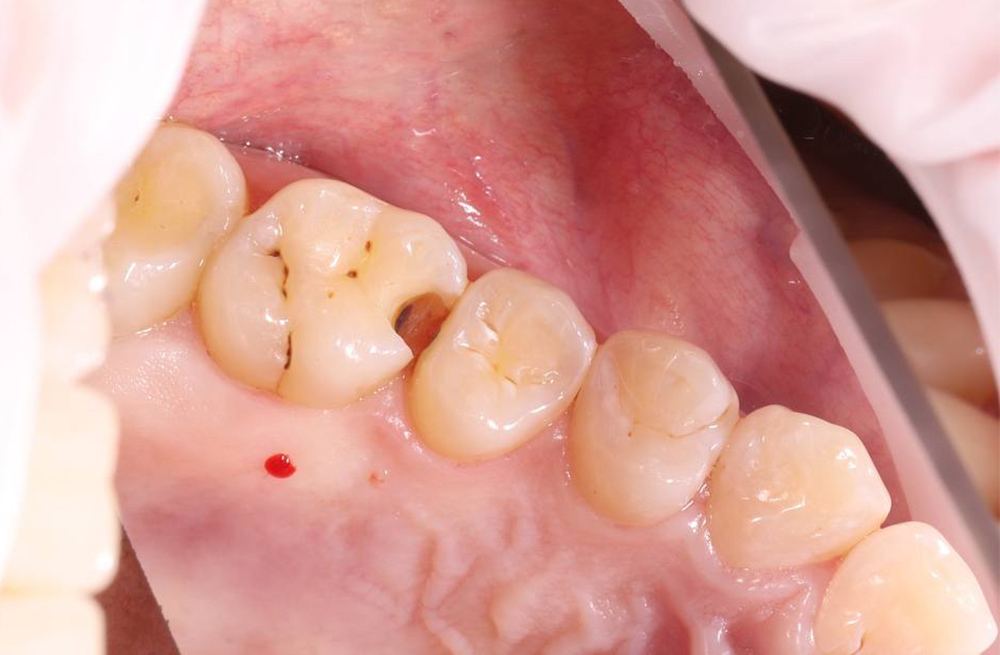

Композитная реставрация жевательных зубов при кариозном поражении